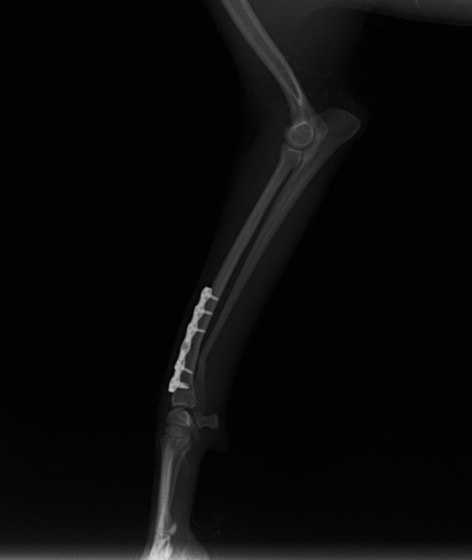

ペルシャ猫 11ヶ月齢 雄

他院にて左大腿骨遠位の成長板骨折(salter-harrisⅠ型)が認められており、治療相談を目的として来院。当院にて、キルシュナーワイヤーを用いたピンニングにより骨折部位の整復を行いました。術後の経過は良好で、現在も経過観察中です。

術前レントゲン

術後レントゲン